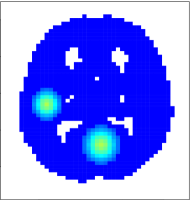

We constructed a 46×55465546\times 55 phantom image using a binary gray matter mask provided by the SPM 8 software package (Welcome Trust, UCL). The selected slice contains 125612561256 voxels within the brain. The field-of-view of the image was assumed to be 192192192 mm. A dynamic image time series of length T=200𝑇200T=200 was simulated as follows. Two task activation profiles x1subscript𝑥1x_{1} and x2subscript𝑥2x_{2}, depicted in the first column of Figure LABEL:fig:act, were created by convolving a canonical hemodynamic response function (Friston et al. 1998) with two task-specific binary stimulus functions.

Activation amplitude maps 𝜷1subscript𝜷1\bm{\beta}_{1} and 𝜷2subscript𝜷2\bm{\beta}_{2} were formed by placing Dirac functions at three separate locations on the phantom image and smoothing each with Gaussian kernels with full width at half maximums (FWHMs) of 101010, 151515 and 202020 mm, respectively. Smoothing was only performed here to generate spatially smooth activation fields; no smoothing was performed on the actual simulated data for the Bayesian GLM. The signal at each voxel v𝑣v was generated by weighting (x1,x2)subscript𝑥1subscript𝑥2(x_{1},x_{2}) by (a1v,a2v)=(1,0)subscript𝑎1𝑣subscript𝑎2𝑣10(a_{1v},a_{2v})=(1,0) for voxels within the first region, (1,0.5)10.5(1,0.5) within the second region, and (0,0.5)00.5(0,0.5) within the third region. The resulting activation amplitudes and activated regions, consisting of locations with activation amplitude greater than zero, are shown in Figure LABEL:fig:act. The baseline field was based on the gray matter prior map, and AR(1) errors with unit variance and autocorrelation coefficient of 0.3 were independently generated at each voxel. In summary, the data at locations v=1,,1256𝑣11256v=1,\ldots,1256 and time points t=1,,200𝑡1200t=1,\ldots,200 was simulated as

We fit model (13) using the proposed Bayesian GLM method. Figure LABEL:fig:mesh displays the triangular mesh, where we see regular triangulation inside the brain and two boundary layers of larger triangles surrounding the brain and within the ventricles. Regions of activation were identified using the joint and marginal PPM approaches with excursion level γ=0𝛾0\gamma=0 and significance levels α=0.05𝛼0.05\alpha=0.05 and 0.010.010.01. For comparison purposes, we also applied the classical GLM method to the simulated data. We first spatially smoothed the data using a Gaussian kernel with 666 mm FWHM, then fit a linear regression model with AR(1) errors to each voxel separately. The AR coefficient was estimated at each voxel by solving the Yule-Walker equations of the residuals of a linear model with uncorrelated errors, then averaging across all voxels. Regions of activation were identified by performing a t𝑡t-test at every voxel, accounting for multiple comparisons with FDR correction or FWER correction. To control the FDR at q=0.05𝑞0.05q=0.05 and q=0.01𝑞0.01q=0.01, we used the Benjamini-Yekutieli procedure for dependent observations (Benjamini and Yekutieli 2001); to control the FWER at α=0.05𝛼0.05\alpha=0.05 and α=0.01𝛼0.01\alpha=0.01 we performed a permutation test by randomly reordering the prewhitened time series of all voxels 100010001000 times, re-fitting the model after each reordering, to estimate the null distribution of the maximum t𝑡t-statistic.

[Uncaptioned image]